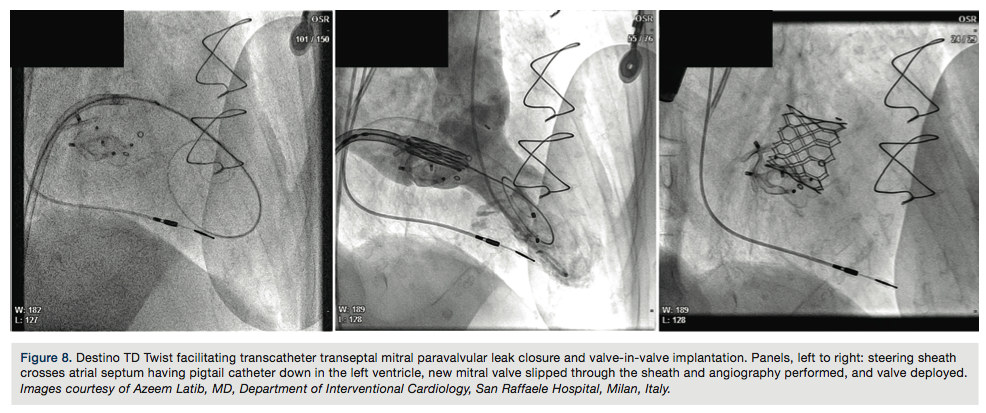

The Destino Twist (Oscor) is a single guiding sheath allowing access to difficult-to-reach vascular anatomy. Cath Lab Digest talks with Dr. Bruno Damascelli and Dr. Vladimira Tichà about their experience with the Destino Twist in procedures such as renal denervation, and its applications for a wide variety of cutting-edge procedures.